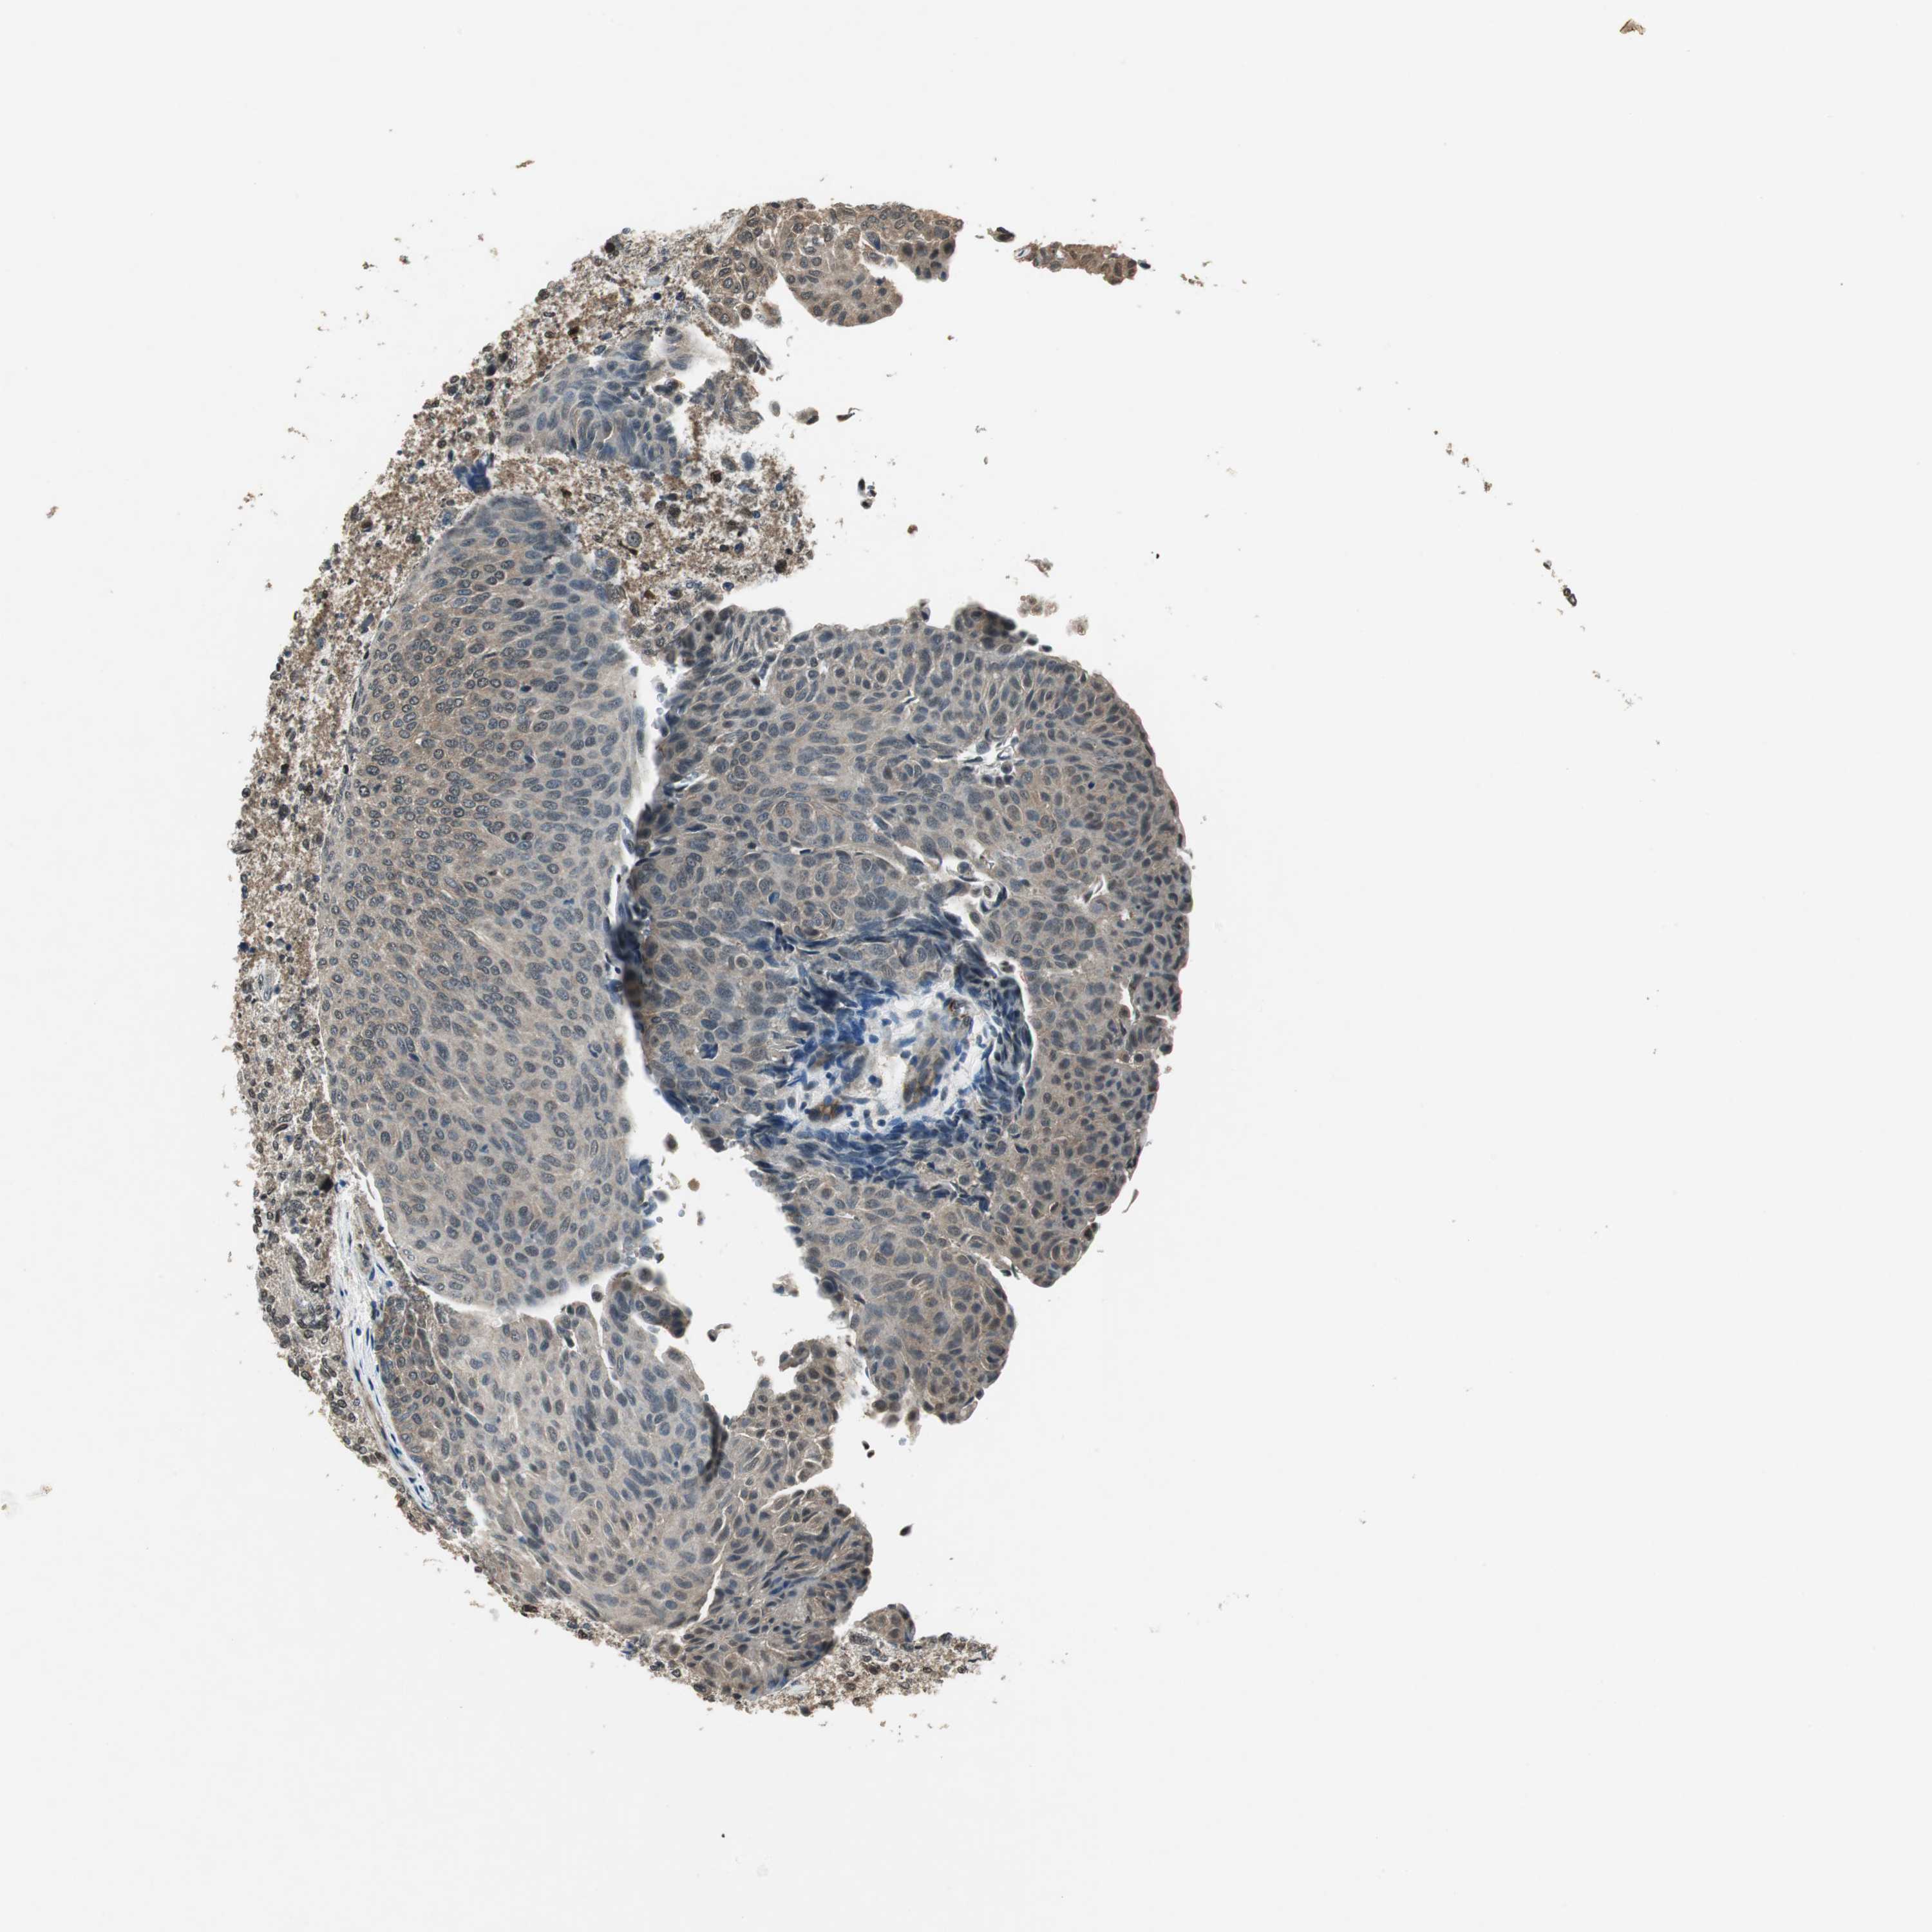

UROTHELIAL CANCER - Protein expressioni

A mouse-over function shows sample information and annotation data. Click on an image to view it in a full screen mode. Samples can be filtered based on level of antibody staining by selecting one or several of the following categories: high, medium, low and not detected. The assay and annotation is described here.

Note that samples used for immunohistochemistry by the Human Protein Atlas do not correspond to samples in the TCGA dataset.

Antibody stainingi

Antibody staining in the annotated cell types in the current human tissue is reported as not detected, low, medium, or high, based on conventional immunohistochemistry profiling in selected tissues. This score is based on the combination of the staining intensity and fraction of stained cells.

Each image is clickable and will lead to virtual microscopy that enables deeper exploration of all samples and also displays staining intensity scores, fraction scores and subcellular localization as well as patient and tissue information for each sample.

Antibody HPA006700

Staining

High

Medium

Low

Not detected

Intensity

Strong

Moderate

Weak

Negative

Quantity

>75%

75%-25%

<25%

None

Location

Nuclear

Cytoplasmic/membranous

Cytoplasmic/membranous,nuclear

Urothelial carcinoma, Low grade

Urothelial carcinoma, High grade